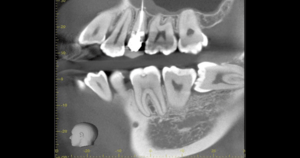

CT

- Before

- After

CTで親知らずと神経(下歯槽管)の位置を確認しました。

親知らずと神経は一定の距離があり、麻痺などのリスクがほとんどないと判断できます。